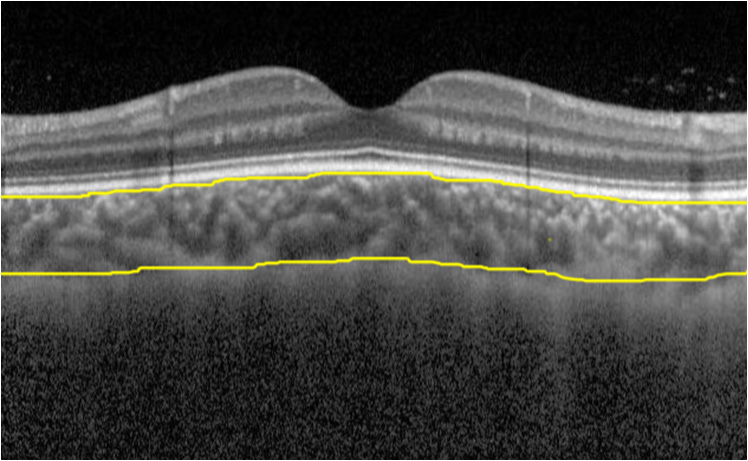

同一名经验丰富的研究人员使用SD-OCT(Spectralis HRA+OCT;德国海德堡工程公司)进行检查,并使用增强深度成像(enhanced depth imaging,EDI)模式优化脉络膜的可见度。利用仪器的自动实时眼球跟踪功能,对每个径向平均进行30次扫描。每个扫描线都是使用仪器的高分辨率扫描模式捕获的,这种高分辨率扫描会产生一个由1 536×3 496像素组成的B超图像。以被检查者黄斑中心凹为中心,对眼底水平及竖直两个方向上的视网膜、脉络膜进行扫描。第二次扫描是通过Follow-up模式从之前的位置采集图像。选取清晰度最高的图像资料进行厚度测量(图1)。为避免昼夜节律影响,由同一位操作员于每日9:00至14:00进行测量[13]。获得OCT图像后,根据扫描结果使用仪器自带的测量系统测量视网膜厚度(retinal thickness,RT),RT是指内界膜至视网膜色素上皮层外缘之间的垂直距离。为了确定测量的重复性,检查者进行用药前后两次黄斑中心凹CT(subfoveal choroidal thickness,SFCT)测量。CT需使用仪器自带的软件进行手动测量,定义为从视网膜色素上皮高反射线的最外边缘到脉络膜巩膜界面内表面的距离[14-15]。每次测量进行3次,取平均值进行记录。分别记录黄斑中心凹RT(subfoveal retinal thickness, SFRT)、SFCT以及距离黄斑中心凹1 mm、2 mm、3 mm上方、下方、鼻侧、颞侧共13个点位的RT及CT(图2),其中SFCT测量值取两次测量的平均值。所有测量结果在所有OCT图像中都得到了很好的识别。

20231026153404_4325.png

图1 CT的测量

Figure 1 Measurement of CT

CT定义为视网膜色素上皮外界与脉络膜巩膜交界处的垂直距离值。

CT was defined as the vertical distance between the outer surface of the retinal pigment epithelium and the junction of the choroid and  sclera.